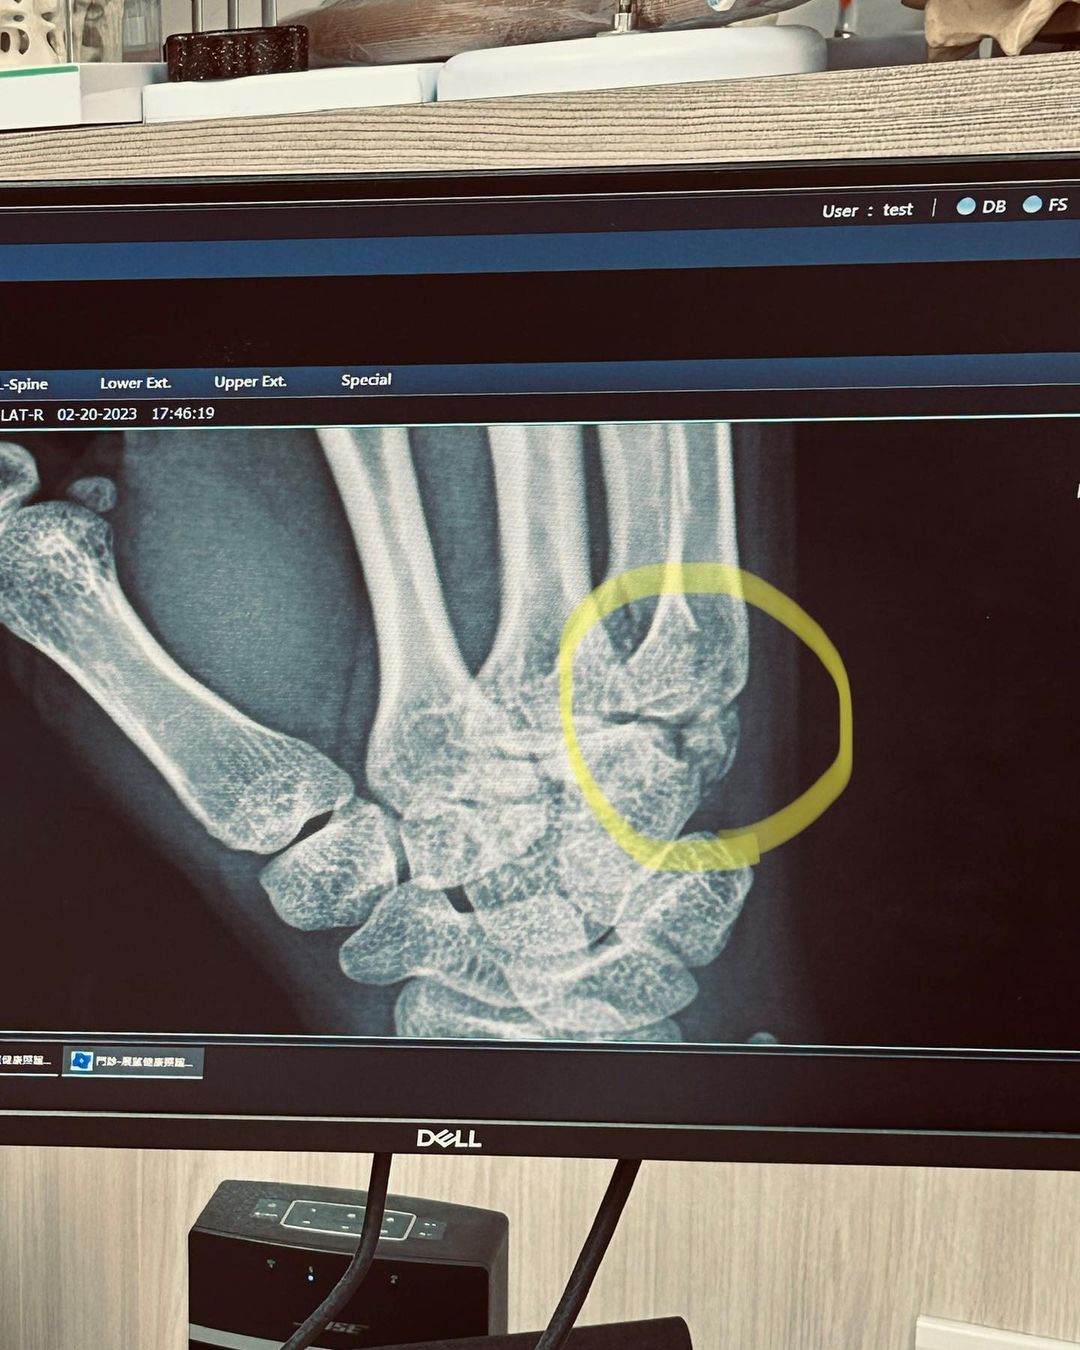

藝人篠崎泫精緻的外型深受觀眾的喜愛,因此經常現身各大綜藝節目,而她私底下也時常在社群平台分享生活,像是2月底就透露因滑倒導致右手骨裂、韌帶撕裂傷,沒想到日前才發現原來左手也骨裂,導致她連打蛋都沒辦法,更無奈表示:「我現在真的一切都好廢」。

篠崎泫2月底曬出手包紮起來的照片,透露事發原因是滑倒用手撐,第一次去醫院時沒被診斷出有異狀,原以為休息幾天就會康復,結果過了一個多禮拜「右手還是不太能動又劇烈疼痛」,再度就診才發現是「骨裂+韌帶撕裂傷」,而接下來幾個月都會用護具固定,讓骨頭慢慢長回來,要大家不用擔心。

不過,篠崎泫5日再度更新病況,她無奈表示:「被誤診兩次。受傷完兩週後,才得知原來左手也有骨裂。」因為雙手都受傷,導致她現在連打蛋都沒辦法,讓她難過表示:「我現在真的一切都好廢」。雖然之前有分享過受傷原因,還是有許多人詢問她的狀況,她再度要大家放心,「也呼籲大家年紀增長,要多注意千萬不要滑倒,通常都偏嚴重,不是尾椎就是手,手算幸運的了,要是尾椎就嚴重了!所以該為我感到慶幸才對~」